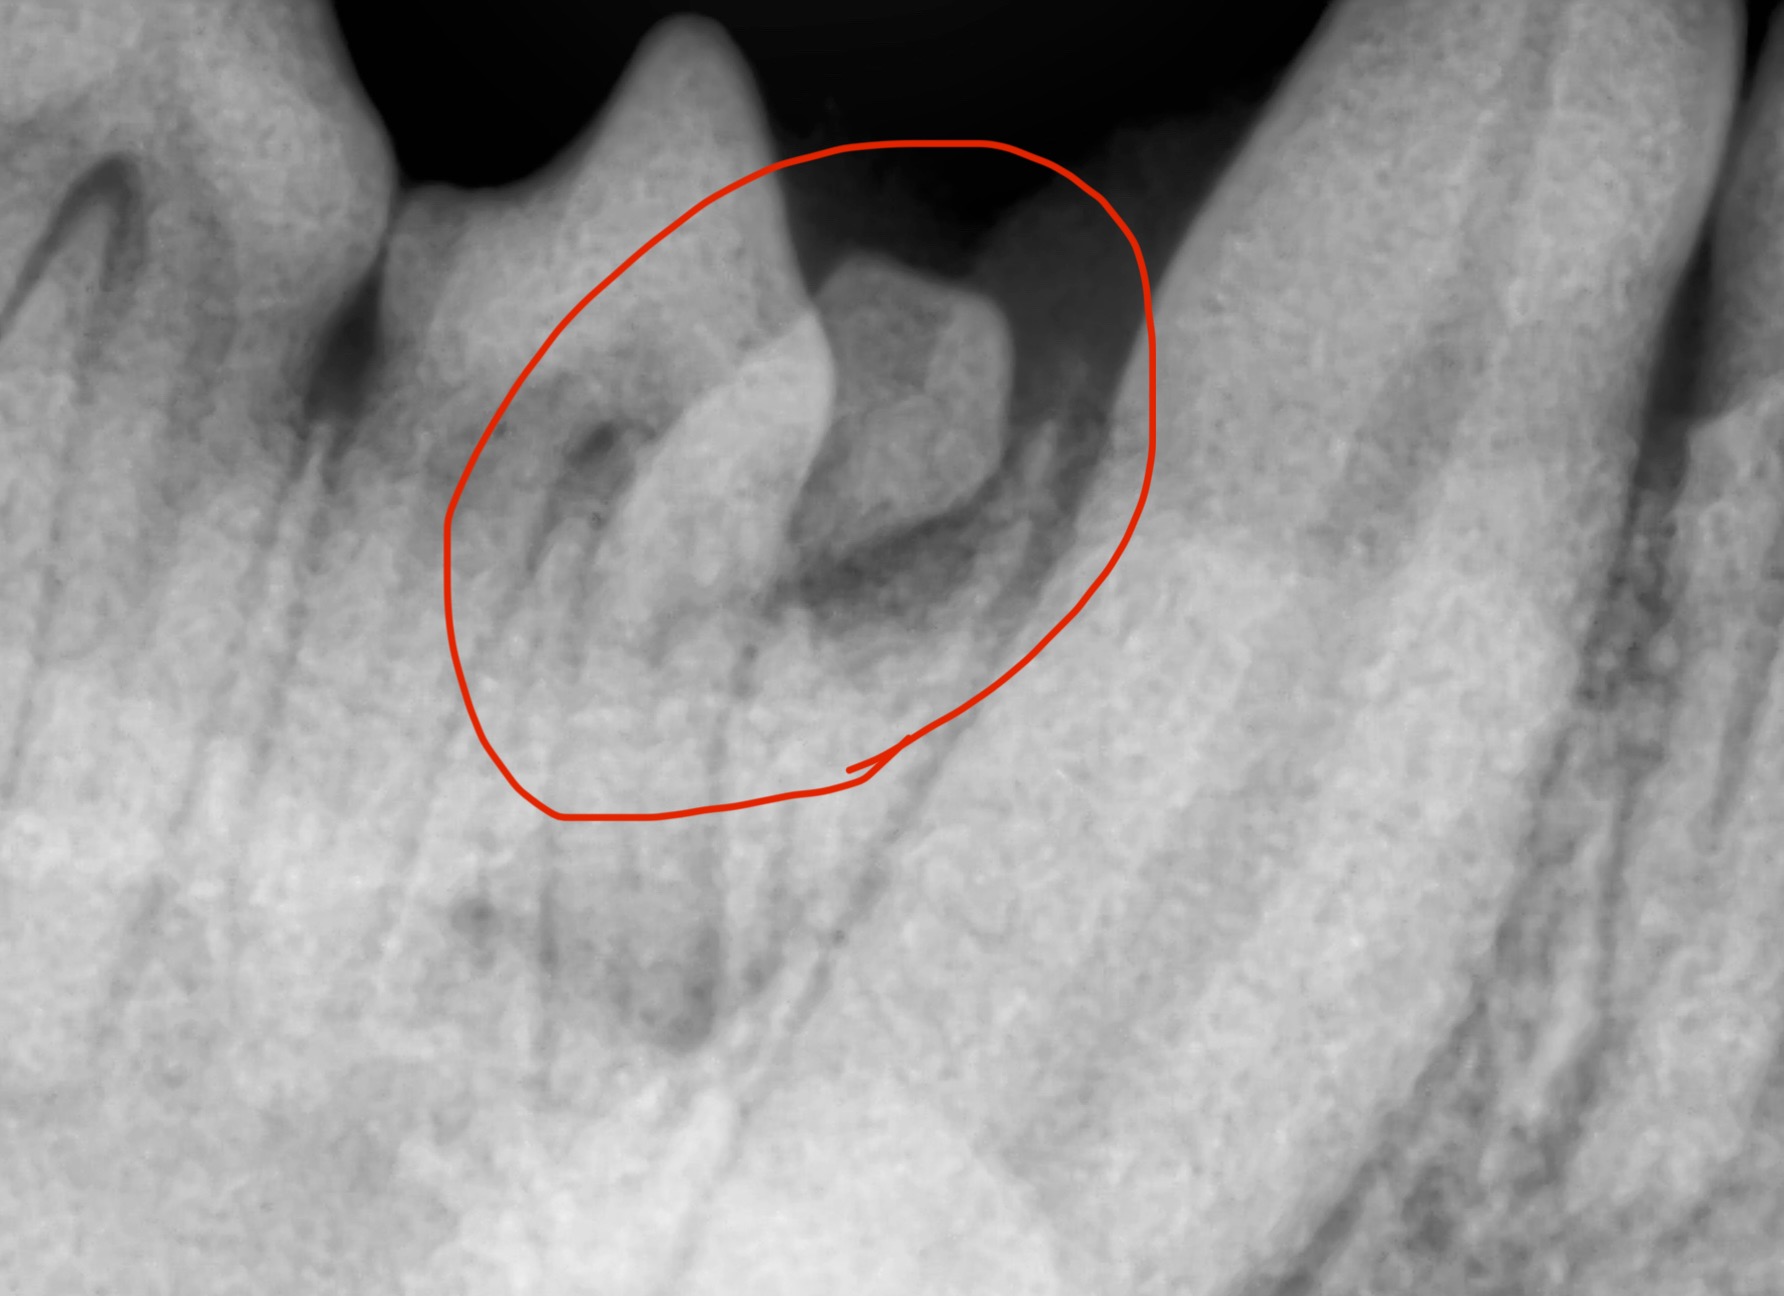

こんにちは! 世田谷区等々力のけいこくの森動物病院です。 愛犬の口の中をじっくり見たことはありますか? 実は、見た目には分かりにくいけれど、気づかないうちに進行してしまう「含歯性嚢胞(がんしせいのうほう)」という病気があります。 今回はこの病気についてご紹介します。 含歯性…

こんにちは! 世田谷区等々力のけいこくの森動物病院です。 今回は、あまり知られていないけれど意外と多い「埋伏歯(まいふくし)」という歯のトラブルについてご紹介します。 「うちの子、歯は全部生えているから大丈夫」「硬いおやつもちゃんと食べてるし、問題ないはず」…